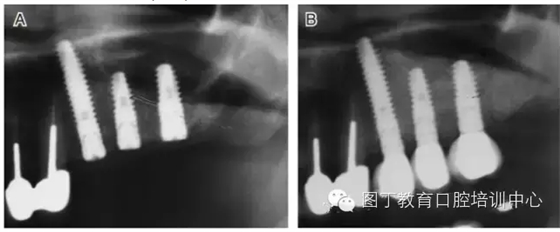

臨床上,可使用曲面體層放射線法及CT掃描方法對(duì)上額竇及可用骨量進(jìn)行評(píng)估。其中曲面體層放射線法可提供多數(shù)病例的硬腭致密影像,為治療計(jì)劃提供有價(jià)值的參考(圖1);而使用CT掃描可提供骨密度信息。如骨高度、密度、牙槽嵴的方向位置,皮質(zhì)骨和松質(zhì)骨的特點(diǎn),上頜竇黏膜厚度,病理狀態(tài)等。顯然,在上頜竇底提升術(shù)中,CT掃描影像的信息對(duì)于手術(shù)設(shè)計(jì)和減少治療風(fēng)險(xiǎn)非常重要。

圖1 采用曲面體層放射線法評(píng)估